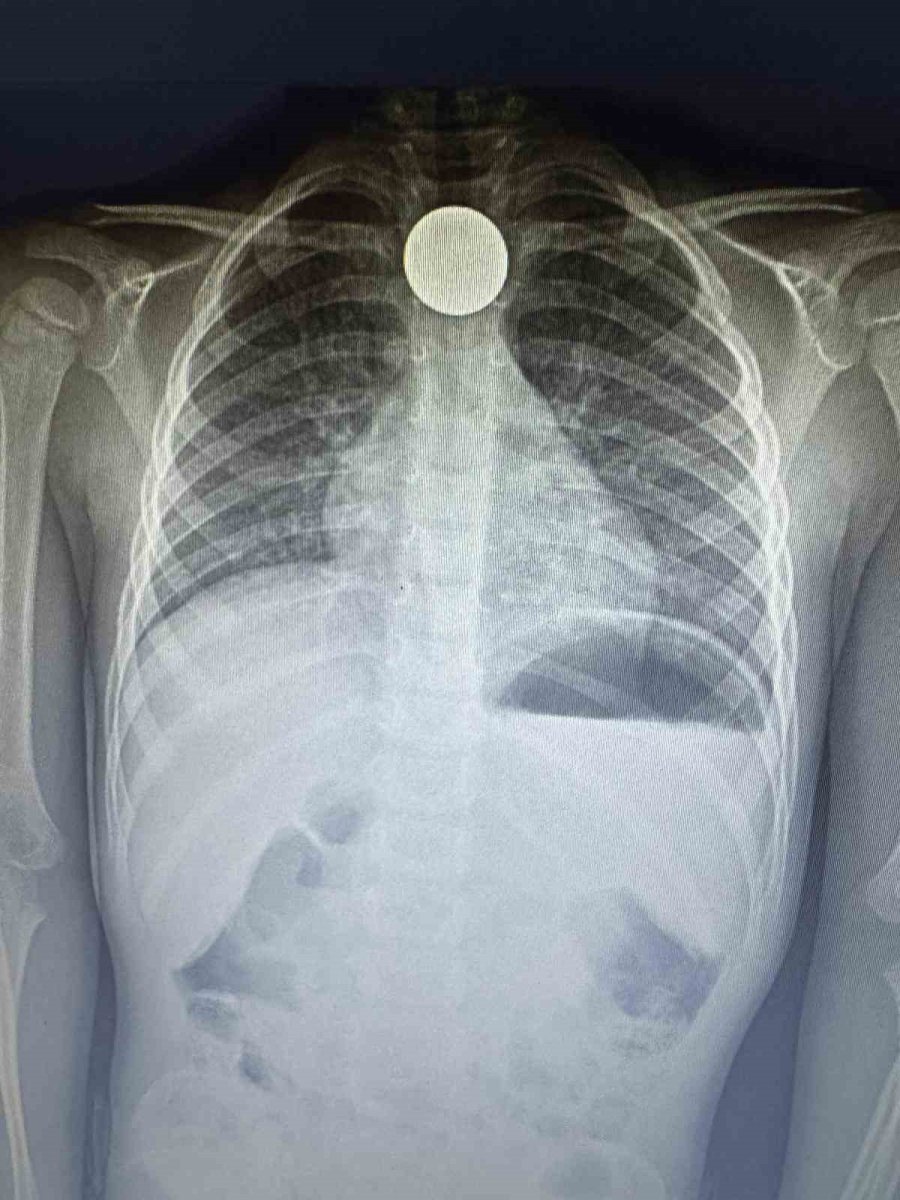

Çekilen röntgende paranın boğazda dik olarak kaldığı görüldü. Doktorlar, paranın yan yatması durumunda küçük çocuğun nefes almasına engel olabileceği ve nefessiz kalarak hayati risk oluşturabileceği aileye anlatıldı. Yapılan 4 saatlik operasyonun ardından para boğazdan çıkarılırken, küçük çocuk ertesi gün taburcu edildi.

Yaşadıklarını anlatan baba Ziya Özden Tezgel, ikizleri Aras Hasan ve Ali'yi okuldan aldıktan sonra eve geldiklerini belirterek, "Çocukları aldığımda Aras Hasan ve Ali'nin okulda Kızılay Haftası ile ilgili etkinlik yaptıklarını öğrendik. Kızılay'a bağış yapmak için biriktirdikleri paraların bulunduğu kumbaralarını getirdiler. Salonda hep birlikte paraları sayıyorduk. Anneleri yemek yaptığı için kısa süreliğine içeriye geçtik. Kısa süre sonra Ali yanımıza geldi. Hasan'ın para yuttuğunu söyledi. Anne çıkarmaya çalıştı ancak olmadı. Antalya Eğitim ve Araştırma Hastanesi'ne götürdük. Çekilen ultrasonda paranın boğazda takılı olduğu görüldü. Doktorlar ameliyata alacaklarını söylediler. Çünkü para Aras Hasan'ın boğazındaki dik duruyordu. İyi ki öyle durmuş, böylece nefes alıp vermesine engel değildi. Doktorlar paranın yan durması halinde çocuğumuzu kaybedebileceğimizi söylediler. 4 saat ameliyatta kaldı. Genelde bu yaştaki çocuklar durumu pek idrak edemiyorlar. Sonrasında ise para ölüme kadar götürebiliyor" dedi.